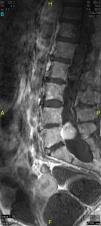

En la resonancia magnética nuclear (RM) lumbar se encontró una lesión expansiva intradural en el cono medular, hipervascularizada y con aporte arterial arrosariado4, desde D10, que ocupaba casi la totalidad del canal raquídeo hasta la altura de L5. Se confirmó por arteriografía espinal un tumor hipervascularizado irrigado por una arteria de moderado tamaño y una gran y tortuosa arteria espinal anterior no candidata a embolización5,6 (figs. 1-3).